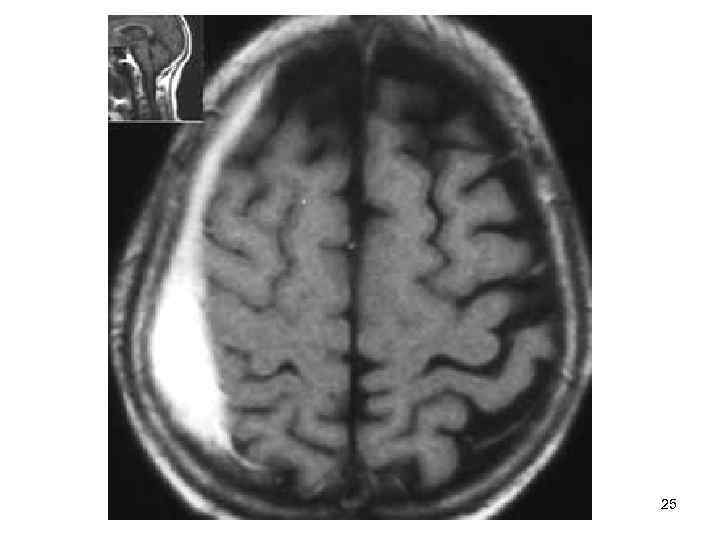

Медицинские аспекты и диагностика субдуральной гигромы мозга